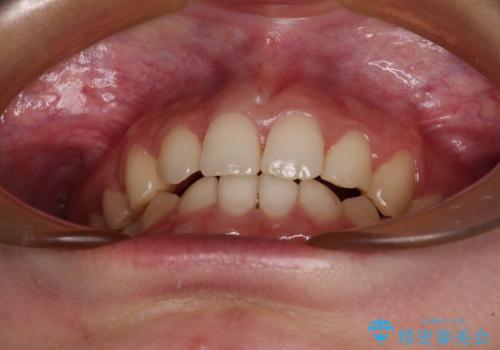

- 下顎前歯が欠損しており、前歯がデコボコとなっている歯並びを気にして来院された患者様です。

下顎の左右側切歯2本が欠損しており、上顎歯列がデコボコとなっている状態でした。

下顎歯列に対して上顎歯列が相対的に大きくなっているため、デコボコとなっているだけでなく、下顎前歯が見えなくなるくらいのディープバイトにもなっていました。